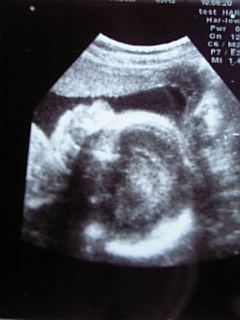

25weeks1days

とうとう、お腹のベビの性別が解りました

上を向いてる姫の横顔。

ハイ。

女の子デシタ~

現在、800g。

頭の大きさ、大腿骨の長さはほぼ週数どおり。

先月までは週数よりちょと小さめちゃんだったけど、いまはちょと大きめ。

経過は順調そう